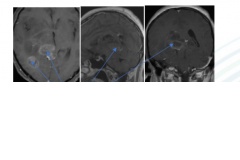

【脑干胶质瘤案例】手术辅助放化疗,较大脑干胶质母细胞瘤术后4年未复发,病史摘要:34岁男性,有6个月的左侧面部感觉丧失、听力障碍、轻度面瘫和右...

【丘脑胶质瘤案例】什么是生命,对于钢琴家来说,手是他的生命。不幸的是,作为钢琴演奏家、钢琴老师的Z女士,大约4个月前发现出右手弹奏不灵活,...

【较大丘脑胶质瘤次全切手术案例】简要病史:39岁男士,在足球比赛中头部轻微外伤后,患者于3个月前开始出现临床症状,轻度复视,于是进一步的诊断...